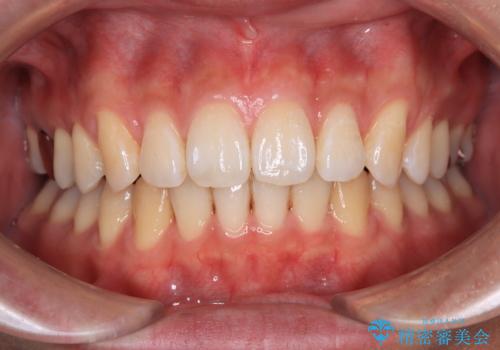

深い咬み合わせと前歯の隙間 ハーフリンガルによる矯正治療

矯正治療中に結婚式があったそうですが、隙間も改善しており、一部装置を外すことなく挙式できたとのことでした。

- 矯正治療後の保定が不十分だと後戻り(元の位置に戻ろうとする動き)をします